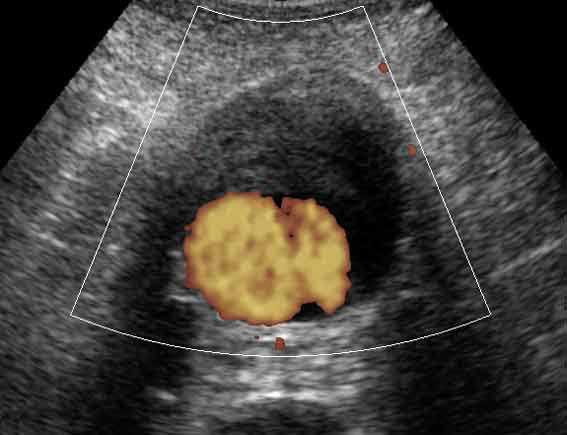

Александр Маркович, на УЗИ в поперечном сканировании ЭТО может выглядеть примерно так:

Вложения

1.jpg

KapustinSV писал(а): ...на УЗИ в поперечном сканировании ЭТО может выглядеть примерно так:

Ну, это ж совсем другое дело!!!